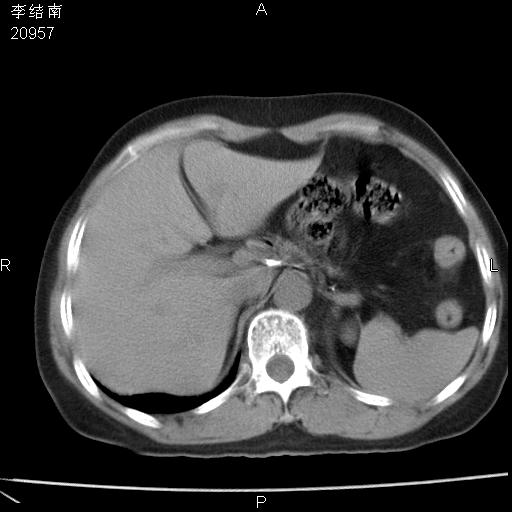

患者女,45岁,以右侧腰部包块来就诊,局部有压痛,皮肤颜色正常。因为是熟人扫的范围较大,患者有胆结石,胆源性胰腺炎病史。请大家看看,有手术病理。

可能大家觉得片子的质量不好,当时是做下腹部扫描,所以没有常规喝水,右腹壁的病灶当时是,密度不均有钙化影,局部骨质没见破坏,肝脏应该是受压的表现,所以当时考虑为腹壁的良性占位,各位老师考虑的神经源性肿瘤,我当时还真没想到,胰腺是胰腺炎治疗后改变.膈脚旁的混杂密度包快不好考虑什么,到上级医院做增强(腹部)+肺部平扫后,发现腹壁的病灶呈不均匀性强化局部可见囊性灶,当时考虑为腹壁结核,最具戏剧性的是膈脚旁的混杂密度灶确是胃的一部分,而腹壁的病灶确是脂肪瘤(简直不可思议)但是我亲眼所见在我们县医院开的.

很不好意思 ,患者后来手术切口裂开,临床医生作了病理证实是腹壁结核。

[病理诊断] CT13183腹壁结核!